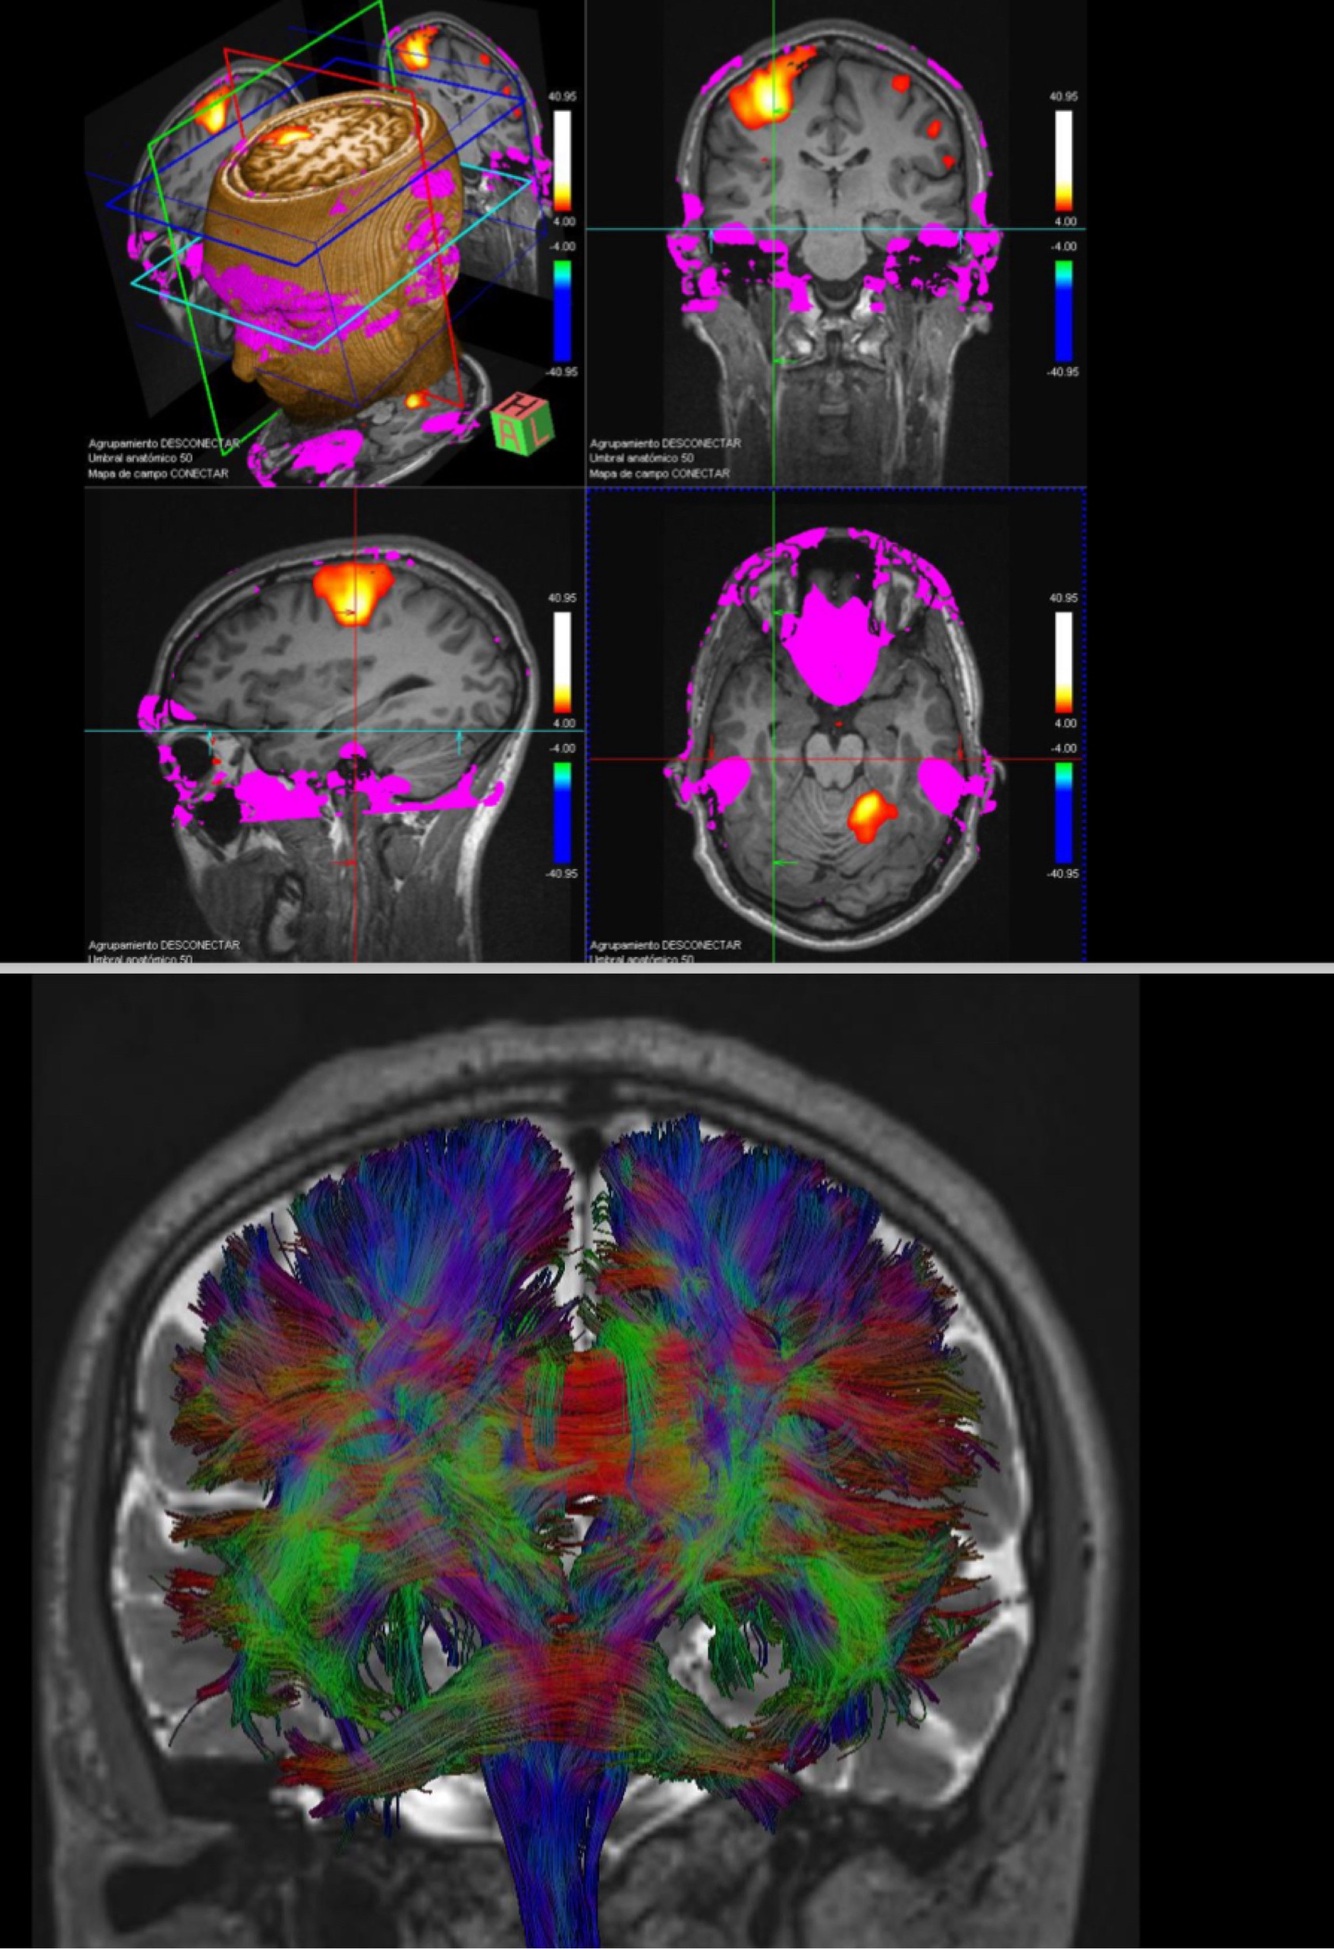

With MRI we can do functional imaging and identify the different areas of the brain (T/F)

A

True: to identify primary motor areas of the hand for example, if we have a tumour we do not see it.

We need the patient to cooperate, to see which area of the brain controls the movement (either speaking for Broca, or moving something for motor cortex).